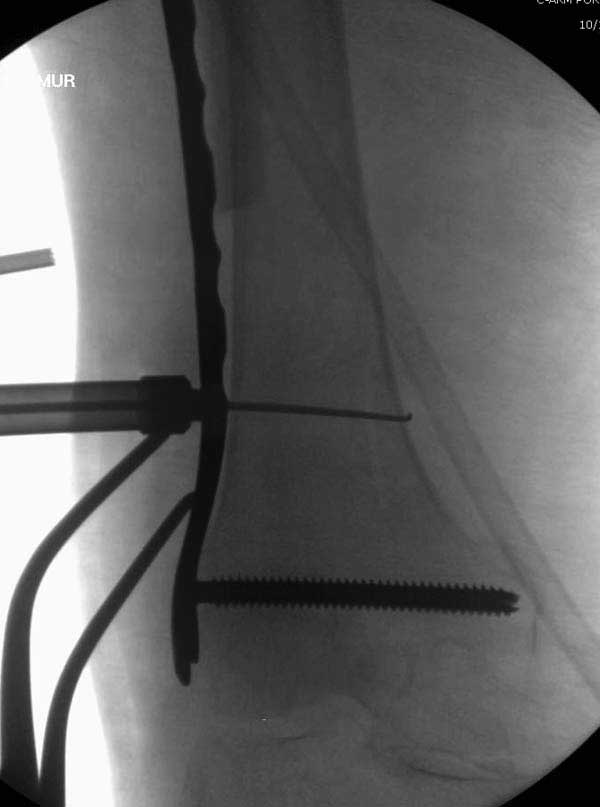

Повторно поступает после двух с половиной лет, где обнаруживается перелом на второй стороне. Немного сложно, но для фиксации выбрали Antegrade InterTan Smith Nephew Nail и с момента фиксации более 3х мес.

Имя     : 25 IT fx Rt  periprosthetic fixation CRM 3.JPG

Тип     : image/jpg

Размер  : 27484 байтов

Описание: отсутствует

Url     : http://weborto.net:8080/pipermail/ortho/attachments/20120509/52aada75/attachment-0047.jpg